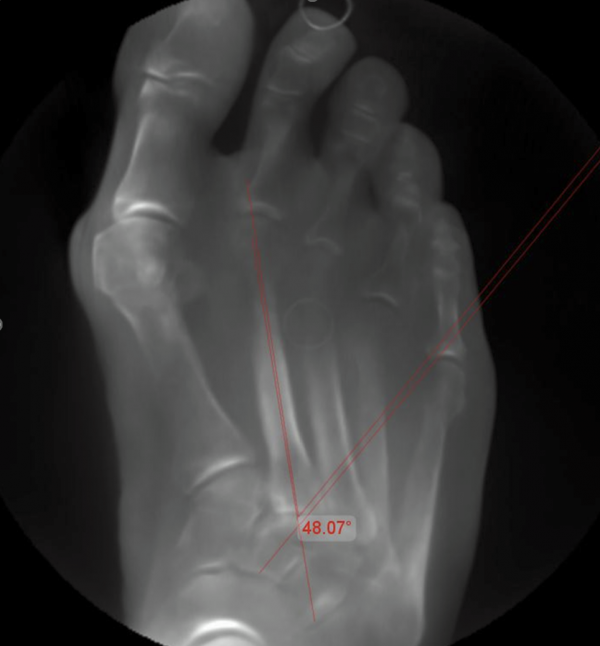

In unserer Praxis nutzen wir bevorzugt den Engel-Winkel — eine Methode, die 1983 von Engel, Erlick und Krems beschrieben wurde und sich seither in der klinischen Praxis bewährt hat [Engel et al., J Am Podiatry Assoc, 1983]. Der Engel-Winkel misst den Winkel zwischen der Längsachse des zweiten Mittelfußknochens und der Längsachse des zweiten Keilbeins auf der belasteten Röntgenaufnahme. Er ist schnell zu bestimmen, gut reproduzierbar und für die klinische Entscheidungsfindung ausreichend genau.

Als Normwert gilt ein Engel-Winkel von unter 25 Grad. Darüber liegt definitionsgemäß ein Sichelfuß vor — je größer der Winkel, desto ausgeprägter die Fehlstellung.

Experten-Tipp: wenn die Längsachse des zweiten Keilbeins (os cuneiforme intermedius) lateral des vierten Mittelfußköpfchens verläuft, liegt fast immer ein erheblicher Sichelfuß vor.